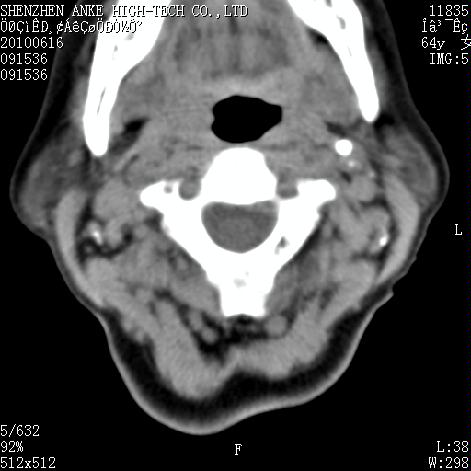

标题: CT27132:患者女,64岁,颈部及全身多处包块,现觉吞咽困难4 [打印本页]

标题: CT27132:患者女,64岁,颈部及全身多处包块,现觉吞咽困难4

右侧甲状腺占位,肿瘤可能性大,癌

右侧甲状腺癌伴右颌下腺淋巴结转移

右侧甲状腺癌伴淋巴结转移

右侧甲状腺癌伴淋巴结转移可能性大

右侧甲状腺癌伴淋巴结转移可能性大。